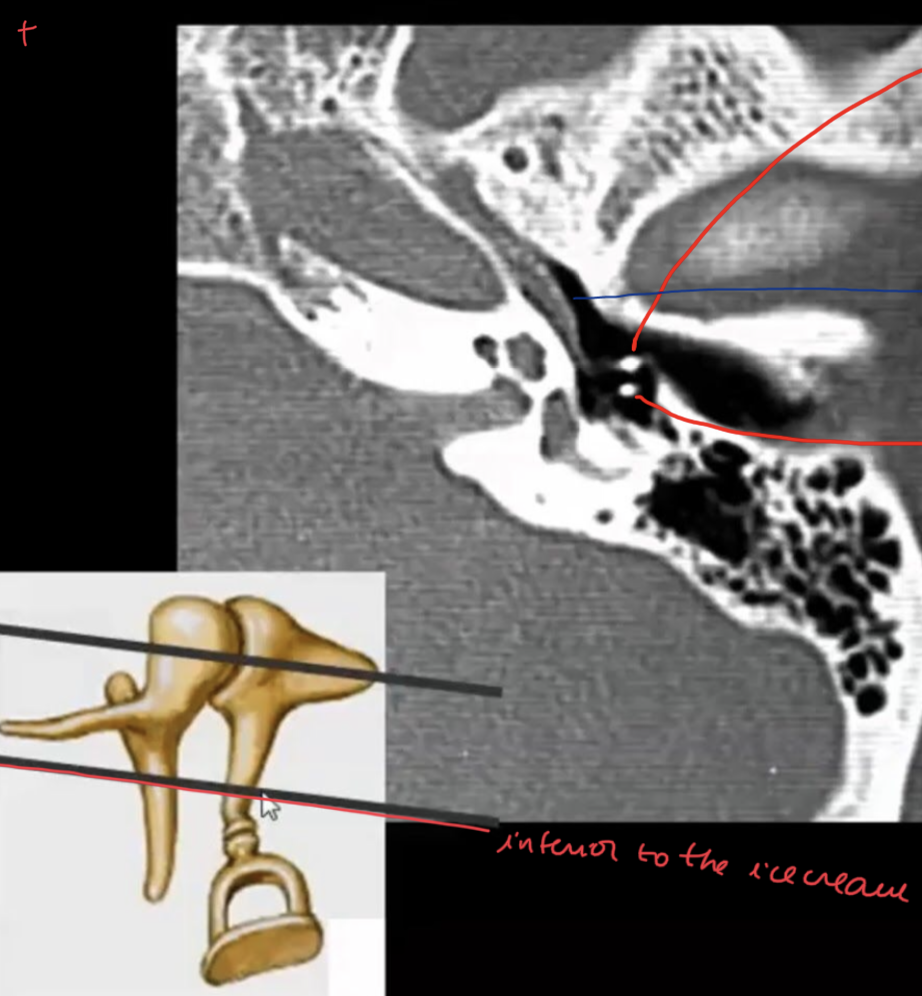

What are the ossicules of middle ear?

Description?